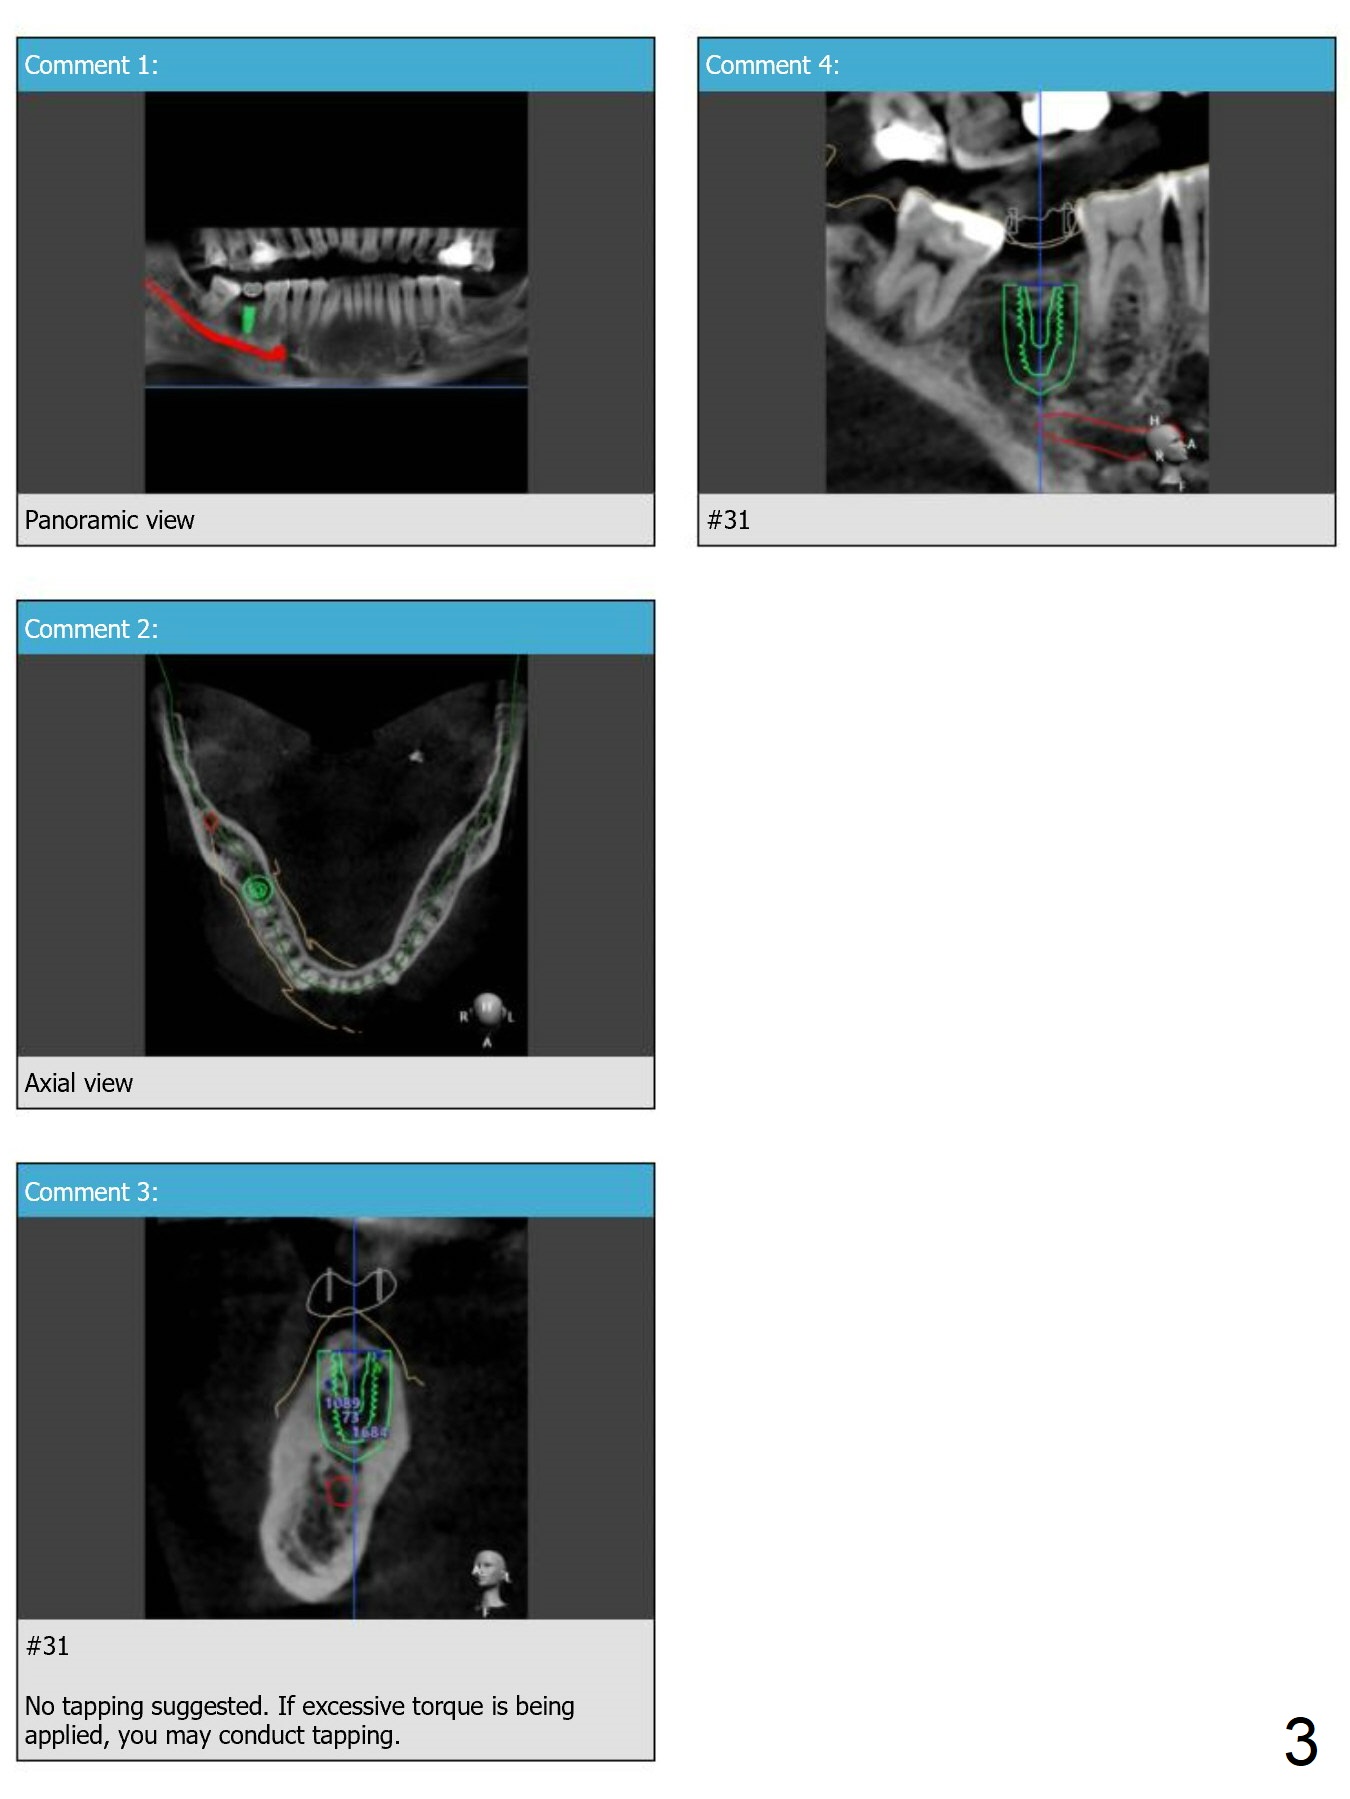

Guide for #31 Placement